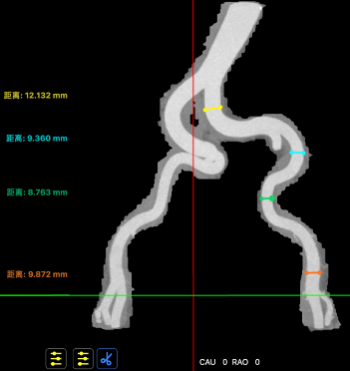

主动脉入路评估

血管入路三维

血管入路MIP(右髂股直径)